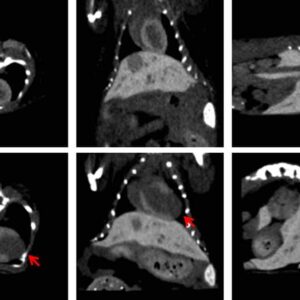

When used with a microCT system, Fenestra HDVC™ enhances soft tissue visibility enabling imaging of organs in PET-CT or SPECT-CT data sets, negative contrast from liver tumors, and vascular systems.

- Tumor Detection: Enhances the visualization of liver and pancreatic tumors, making it easier to identify even small masses for oncology studies.